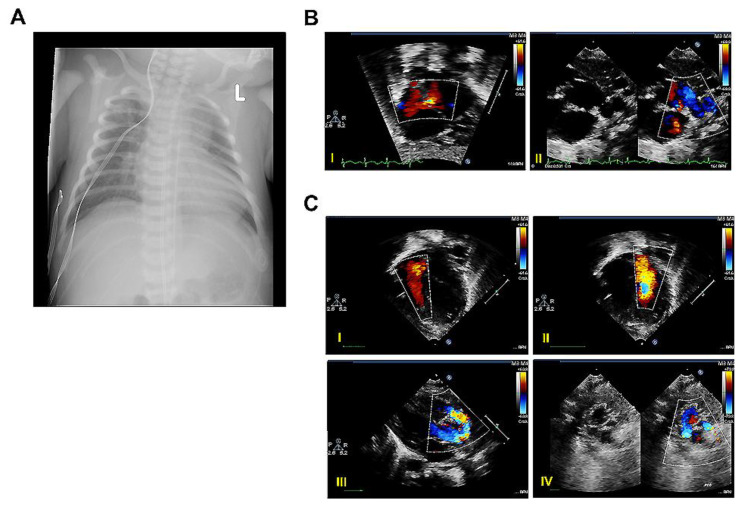

图 5.患儿B的临床特征

患儿B的临床特征。( A ) 生命第0天(DOL 0)的代表性胸部X光检查显示心脏扩大。左:左。( B ) DOL 0的代表性超声心动图图像。( I )心房球囊隔膜成形术后心房内通讯的彩色多普勒图像;( II )显示动脉导管未闭的彩色多普勒图像。( C ) DOL 6的代表性超声心动图图像。( I、II )三尖瓣( I )和二尖瓣( II )的彩色多普勒图像;( III )动脉调转术后主动脉弓的彩色多普勒图像;( IV )动脉调转术后肺动脉分支的B型和彩色多普勒图像。